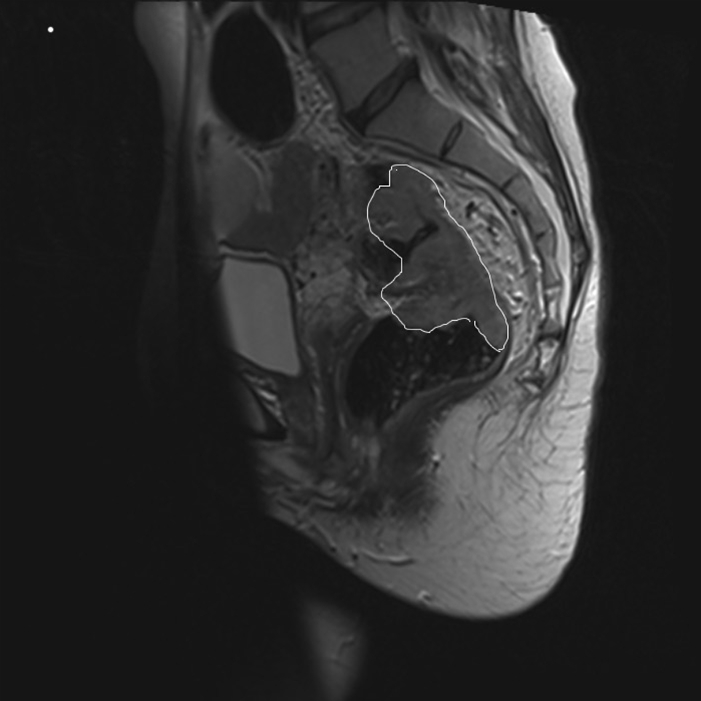

Colorektal cancer, MR, længdesnit

Billedet viser en MR-skanning af en rectumcancer i længdesnit. Den store tumor (markeret) er beliggende i den øvre del af rectum.